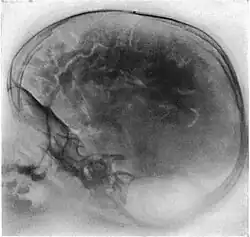

Pneumoenzephalogramm

Die Pneumoenzephalographie oder Pneumoenzephalografie, auch Pneumoencephalografie, deutsch auch Luftenzephalographie (oder Luftenzephalografie), ist eine kontrastverstärkende Methode, oberflächliche Strukturen des Gehirns in konventionellen Röntgenaufnahmen als Pneumoenzephalogramm darzustellen. Sie wurde 1918/1919 vom amerikanischen Neurochirurgen Walter Edward Dandy eingeführt.[1][2][3] Diese Methodik galt damals als Meilenstein der Diagnostik, doch sie ist heute obsolet.

Bei einer Pneumoencephalografie wird der Liquor cerebrospinalis über einen lumbalen (siehe: Lumbalpunktion) oder subokzipitalen Zugang abgesogen und in gleichem Maße Luft eingeleitet. Durch Lagerung des Patienten kann nun erreicht werden, dass sich die Hirnwindungen gegen die Luft sehr deutlich abzeichnen. So konnten in vivo bei geschlossener Schädeldecke erstmals die Hirnwindungen radiografisch dargestellt werden und so bei neuralen Auffälligkeiten der Verdacht auf Tumore, Schwellungen oder Malformationen abgeklärt werden. Auch konnten so abgekapselte Hämatome (subdural wie epidural) sichtbar gemacht werden.